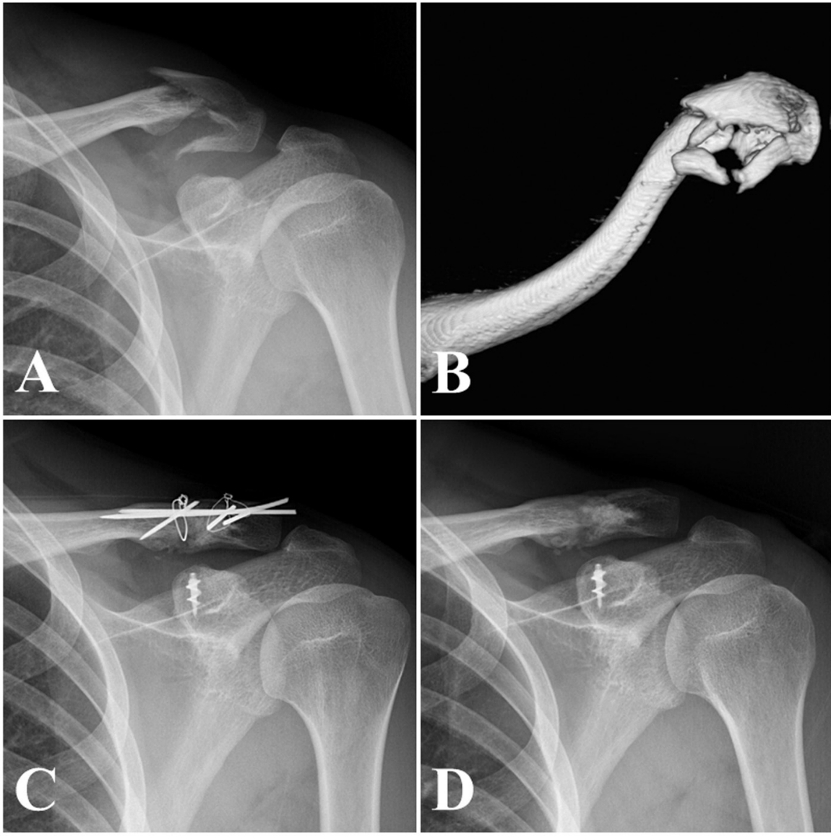

铆钉结合张力带克氏针固定后再次骨折,但转化为中段骨折,予以钢板固定